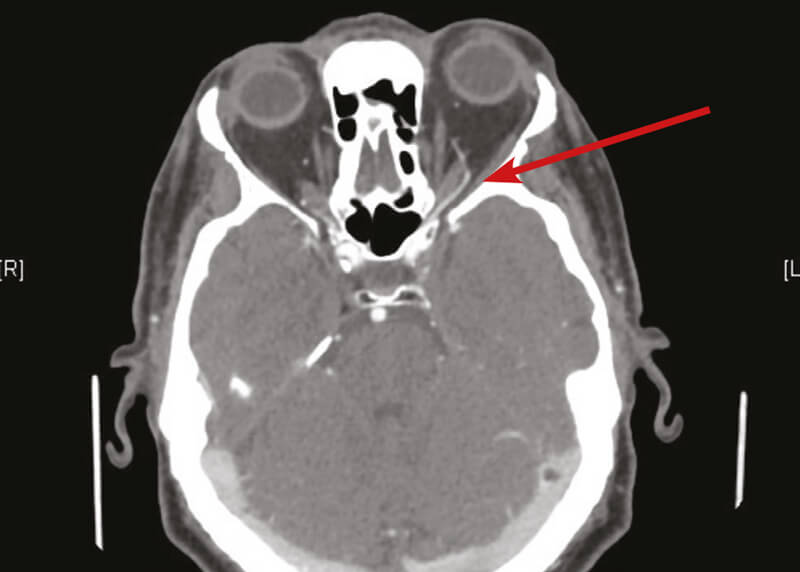

On ocular examination, his visual acuity was excellent at 6/6 in both eyes. Slit-lamp examination showed bilateral pseudophakia, with moderate left proptosis, lid and conjunctival chemosis, mildly raised intraocular pressure and a left VI nerve palsy (Figures 1 and 2). He had blood tests for full blood count (FBC), erythrocyte sedimentation rate (ESR), C-reactive protein (CRP) and thyroid function tests, as well as a brain and orbits CT scan plus angiogram (CTA) as the clinical signs were very localising to the left orbit / left cavernous sinus.

The CT / CTA findings confirmed the proptosis and enhancement of the left cavernous sinus as well as the left superior ophthalmic vein confirming the carotid - cavernous fistula (Figures 3 and 4).

Figure 4: Enhancement of left superior ophthalmic vein suggestive of left CCF (red arrow).